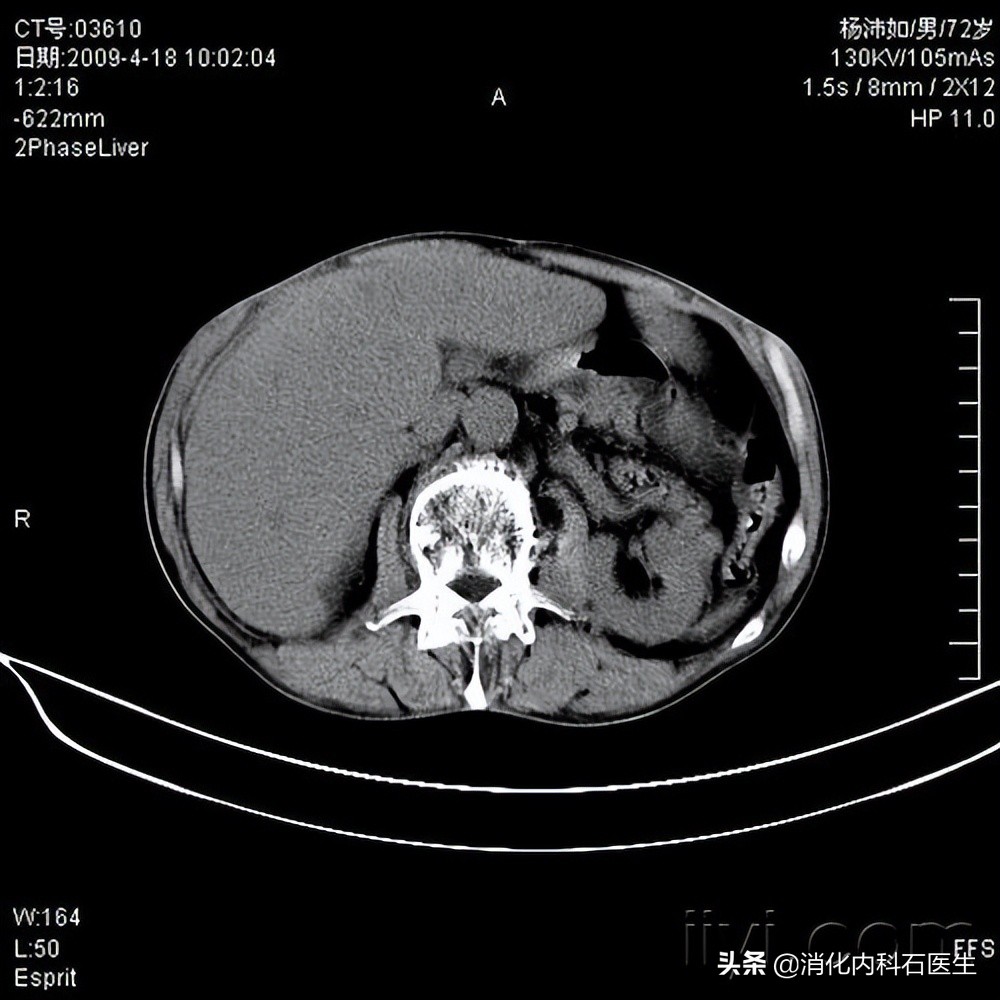

上腹部CT一扫:未见明显异常。